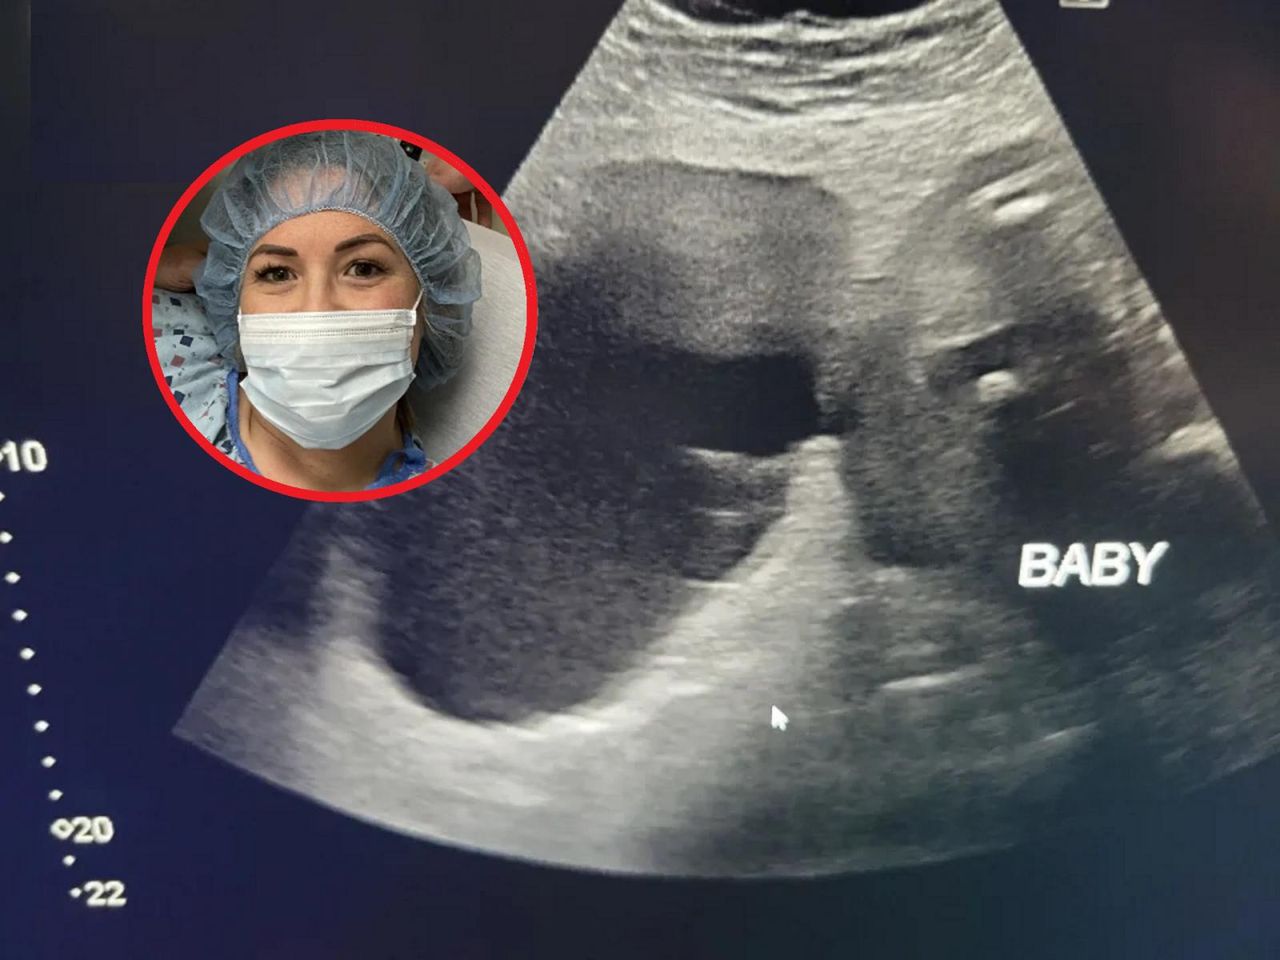

Laura to 30-letnia mama czwórki dzieci. Z narodzinami jej czwartego dziecka, Lennoxa, wiążę się przerażająca historia. Wraz z partnerem Anthonym Lewisem przyznali, że nie było problemów z ciążą, dopóki Laura nie musiała być indukowana w 42. tygodniu. Laura swój poród wspominała jako bardzo traumatyczny, kiedy jej dziecko przyszło na świat, było wiotkie i wiedziała, że coś jest znim nie tak.

W wywiadzie dla The Liverpool Echo przyznała: "Poród był absolutnie przerażający i został wywołany w 42. tygodniu".

Od razu po narodzinach Lennoxa Laura wiedziała, że jej dziecku coś dolega. Jednak lekarze na początku byli innego zdania:

"Kiedy się urodził, zauważyłam, że jest wiotki, lekarze stwierdzili, że jest po prostu leniwym dzieckiem i cztery godziny po porodzie odesłali nas do domu. Miałam problemy z karmieniem, ale powiedziano nam, że to z powodu leków, które brałam i w ciagu kilku dni powinno sie to ustabilizować.

Jednak gdy położna przyszła sprawdzić jej synka, okazało się, że stracił 13 proc. swojej masy ciała, która wcześniej wynosiła 4 kilogramy.

Rodzina ostatecznie zabrała noworodka do szpitala z powodu problemów z karmieniem i ciągłą sennością.